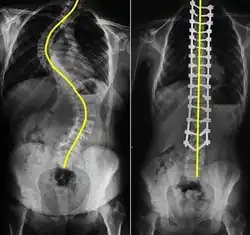

RSP could be a symptom of some medical conditions, such as kyphosis, scoliosis, forwarded head posture or ankylosing spondylitis.[23] Kyphosis is a spinal disorder that contributes to excessive curvature of the upper back,[24] leading to a hunched posture and RSP. Scoliosis refers to a condition where there is a sideways curve in a person's spine,[25] causing our shoulders to become uneven and rounded.

Imaging tests

Imaging tests such as X-rays, CT scans and MRI[7] scans are used to determine the cause and extent of RSP.